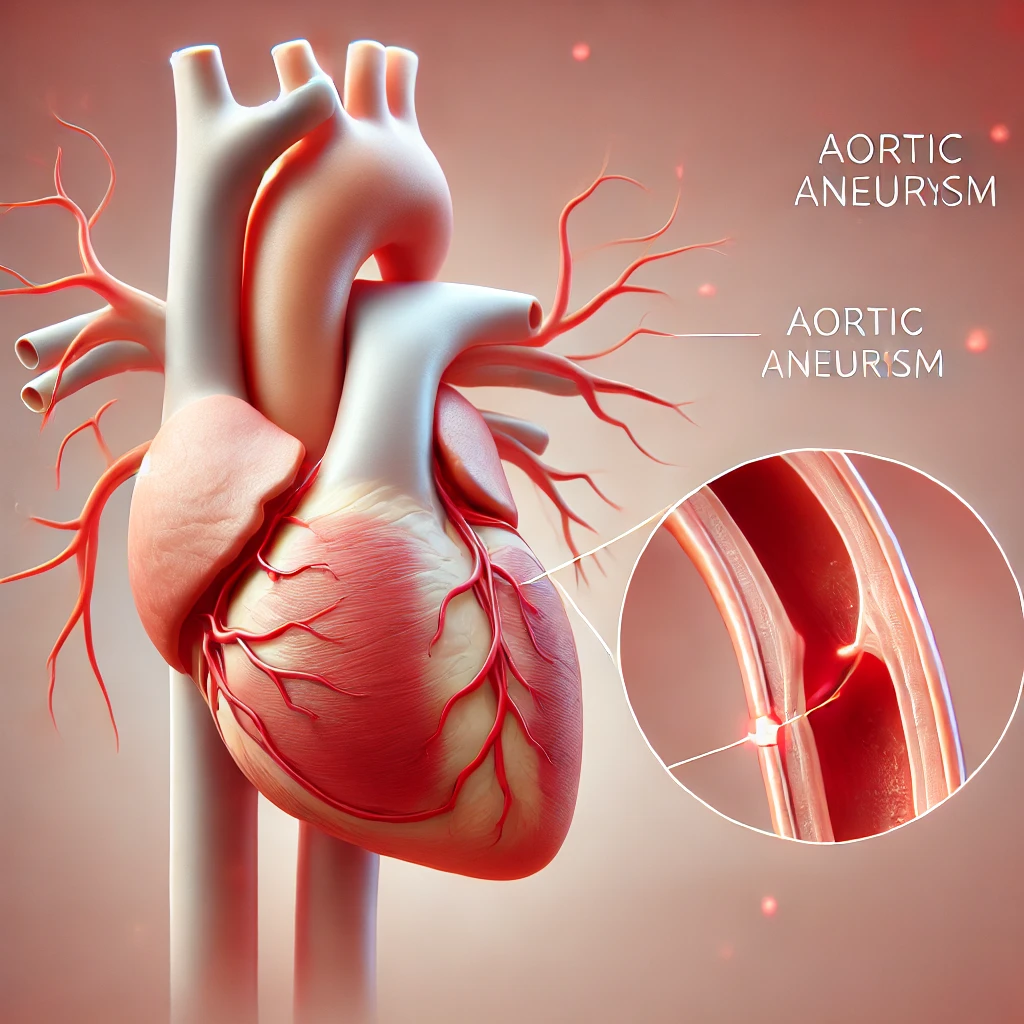

مقالات طبية من مساهمات الأطباء